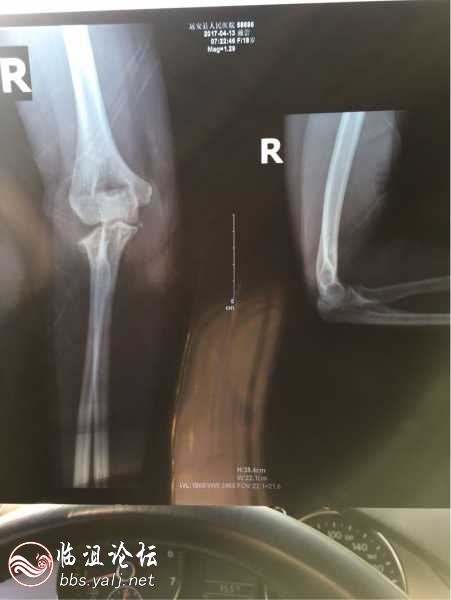

4.13号6点25分左右,原人大副主任张**把我女儿撞成右手肘骨折,在宜昌市一医院做的手术。肇事者如今不管不问!远安县交警大队民警王**(警号:061862)、徐**(警号:061676)颠倒黑白、徇私枉法!做出让人匪夷所思的裁决,正义在哪里?公平在何方???对于马上就要参加高考的高三学生,伤了右手,对她的前途不可预知!显而易见的视频,竟然判我女儿负主要责任,公平在哪里???良心在何方???

事故经过:2017年4月13日6时25分,戴某(女,汉族,现年18岁,户籍地:远安县鸣凤镇北门街1号,居民身份证号:42052519980725****),驾驶自行车沿远安县鸣凤镇解放路由南向北行驶至解放路23号门前路段处,遇前方张某某(男,汉族,现年73岁,户籍地:远安县鸣凤镇解放路25号,居民身份证号:42272519440517****),驾驶自行车与其同向行驶,戴某驾驶自行车从张某某的右侧超车时,恰遇张某某向右转弯,双方避让不及相碰撞,造成戴某受伤及其自行车受损的道路交通事故。事故发生后当事双方均离开现场,当日9时许,戴某的母亲向我队报警。在此事故中,戴某经宜昌市第一人民医院诊断证明右桡骨头骨折和右尺骨骨折。